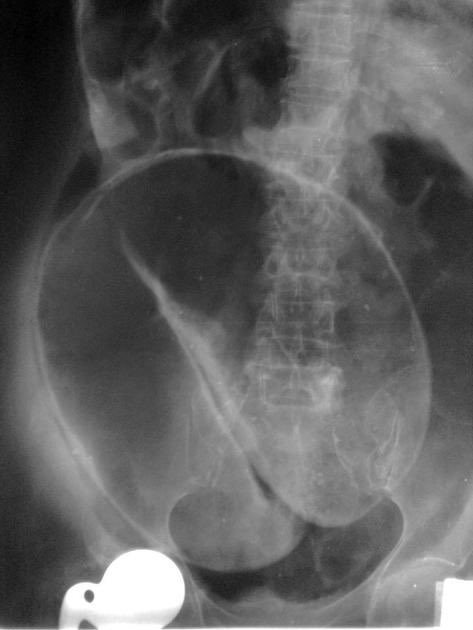

📍Sigmoid Volvulus (coffee bean sign)